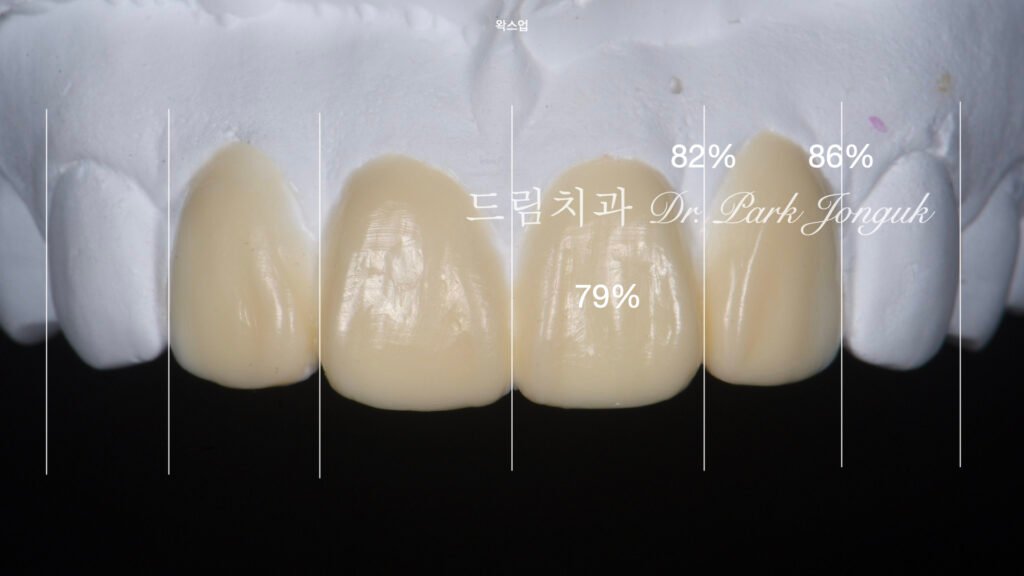

왁스업 설계: 비율의 과학

사진 2는 왁스업 정밀진단(Diagnostic wax-up) 과정입니다.

비율의 중요성

압구정 드림치과 박종욱 원장은 **”비율을 맞추는 게 중요하다”**고 강조했습니다. 심미 치과에서 **비율(Proportion)**은 색상이나 투명감만큼 중요한 요소입니다.

황금 비율의 적용

중절치와 측절치의 **조화로운 폭 비율(Harmonious width ratio)**을 설정했습니다. 일반적으로 중절치:측절치의 이상적 비율은 약 1.6:1 (Golden proportion) 또는 환자의 안면 특성에 맞춘 개별화된 비율입니다.

**치관 길이-폭 비율(Crown length-to-width ratio)**도 최적화하여 과대하거나 과소하지 않은 자연스러운 크기를 설정했습니다.